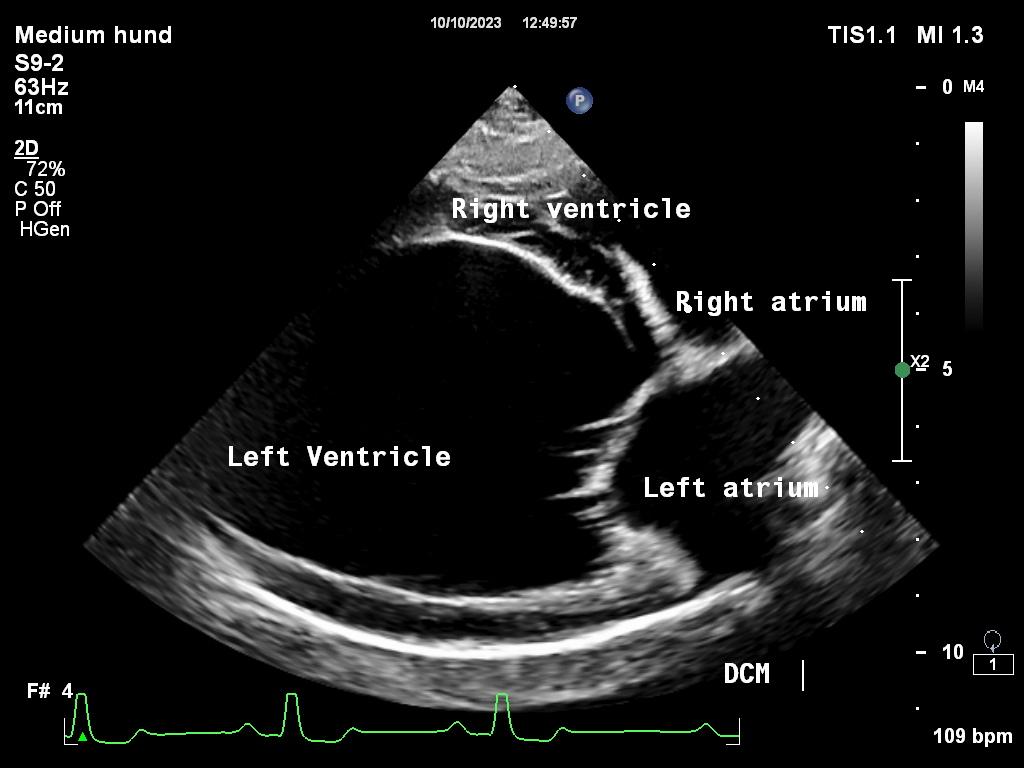

Dilatert kardiomyopati – DCM

Dilatert kardiomyopati (DCM) er en fellesbetegnelse for hjertesykdom som fører til at hjertet får nedsatt pumpefunksjon. DCM er genetisk nedarvet hos enkelte hunderaser som dobermann, Irsk ulvehund, grand danois og andre store raser. Andre årsaker til DCM er betennelse i hjertemuskelen (myokarditt), rytmeforstyrrelser (arytmi), feilernæring, eller som følge av annen systemisk sykdom.

For å stille diagnose samt gradere sykdom utfører en kardiolog, en dyrlege som har spesialisert seg på hjertesykdommer, en ultralydundersøkelse av hjertet til hunden. Ved mistanke om hjertesvikt tar vi i tillegg røntgenbilder av brysthulen eller ultralyd av lungene for å se om det er væskeansamling i lungene. Er det mistanke om rytmeforstyrrelser, eller hunden kollapser, er det aktuelt med EKG undersøkelse.